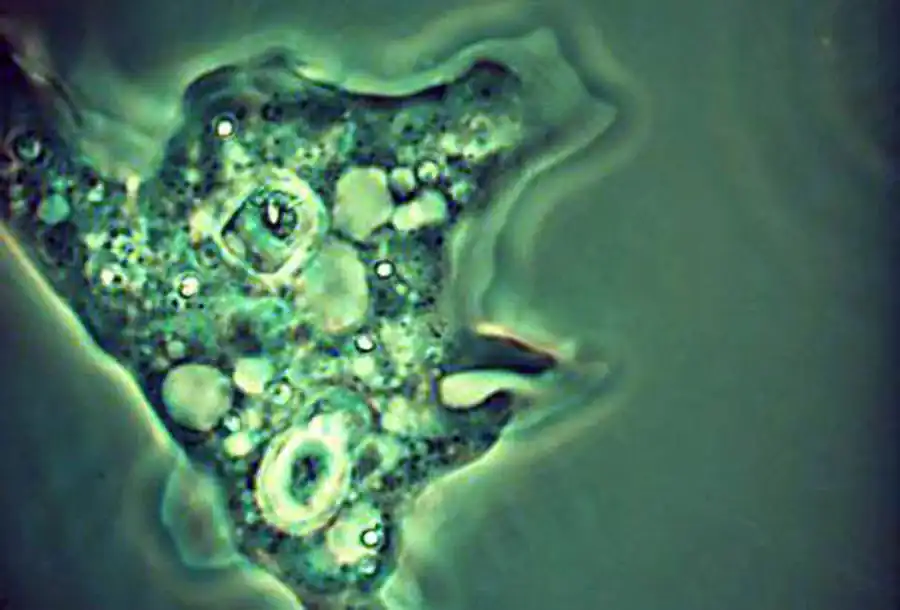

Entamoeba histolytica. I — тканевая форма; II — просветная форма; III — V — одно-, двух- и четырехядерные цисты

Тканевая форма представляет собой очень подвижную амебу с пузырьковидным ядром. Протоплазма резко разделяется на стекловидную эктоплазму и зернистую эндоплазму. Широкие тупые псевдоподии состоят из эктоплазмы. Характерно внезапное толчкообразное возникновение псевдоподий. В эндоплазме тканевой формы дизентерийной амебы всегда встречаются заглоченные эритроциты, которыми она питается, что отличает ее от просветной формы и от всех остальных кишечных амеб человека.